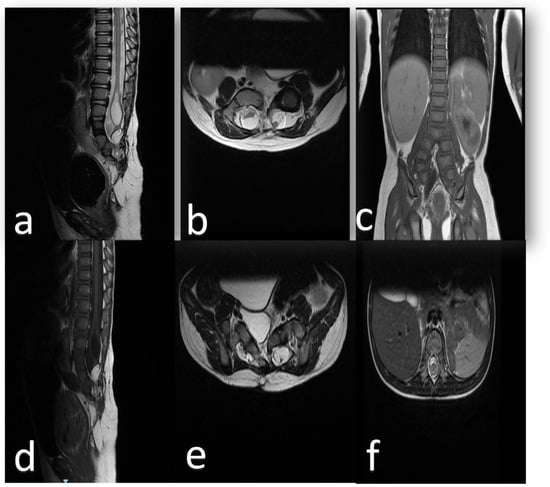

2. Clinical Presentation